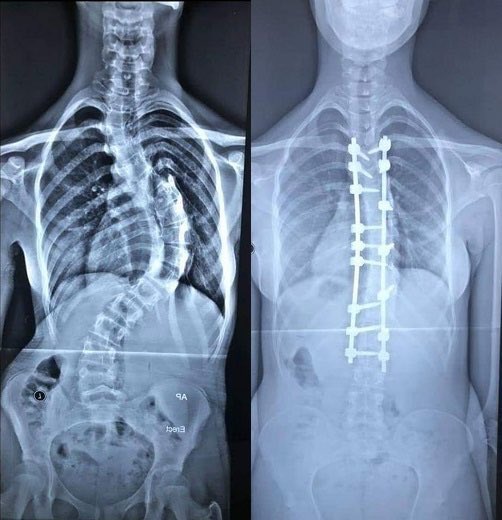

فتاة في زهرة شبابها (١٨عام) تعاني من تشوه في العمود الفقري وتحتاج إلى عملية جراحية لتعديل الانحراف.

هذه الصور توضح معنى انحراف العمود الفقري.